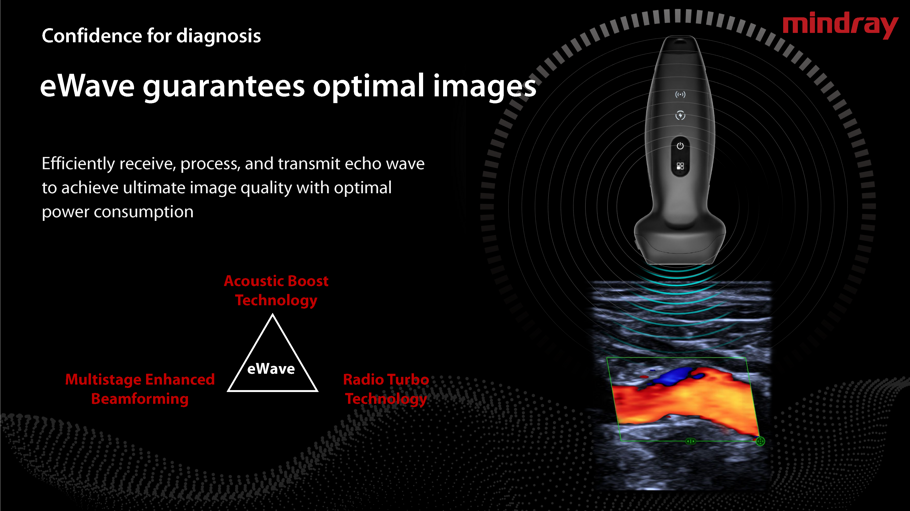

TE Air, il sistema ecografico portatile wireless di nuova generazione di Mindray, è progettato per soddisfare questi requisiti clinici più elevati, come l'emergenza e la terapia intensiva. Combinando funzionalità premium con un'esperienza wireless, una connettività efficiente e un design robusto per ambienti imprevedibili, il sistema ecografico portatile wireless TE Air aiuta a migliorare la fiducia e l'efficienza dei medici in modi senza precedenti.

- Sonde a frequenza variabile,Color Doppler,Pulsed Wave,Power Doppler.

- Armonica di tessuto,Spacial Compound ,Connessione WiFi e USB ,velocità wireless elevato.